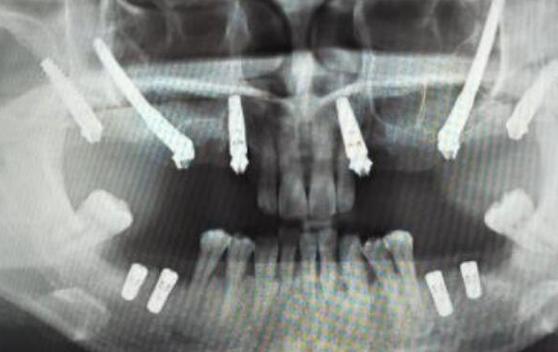

- 务必进行CBCT检查: 这是评估上颌窦位置、骨高度、骨质量的金标准,没有CBCT,无法准确判断“近”到什么程度,以及是否需要提升。